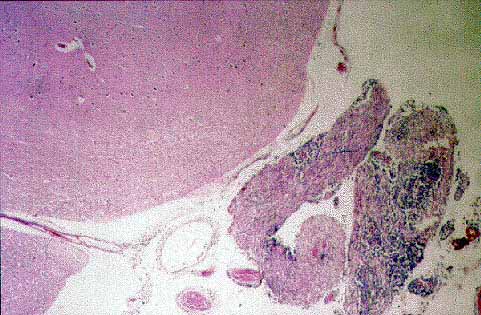

figura 5

Figura 5.Infiltración subaracnoidea por el linfoma. H-E x10